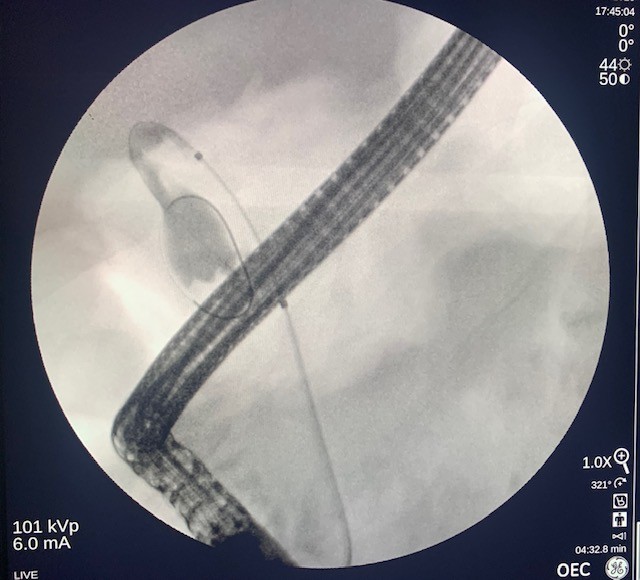

The gastroscope (Olympus, America) was passed into the esophagus under direct visualization. The esophageal and gastroesophageal junction appeared fine without inflammation or lesions. Examination of the stomach showed portal hypertension gastropathy without gastric varices. The duodenal bulb and second part of the duodenum were also clear without pathology. Next, the linear array echoendoscope (Olympus) was passed into the esophagus and advanced into the stomach. EUS imaging revealed a cirrhotic liver surrounded by a large amount of ascites (Fig 1). From the duodenum, the gallbladder was assessed and demonstrated signs of gallbladder wall thickening with a large burden of sludge and small stones (Fig 2).

Figure 1. Endoscopic ultrasound of the liver with significant ascites present.

Figure 1